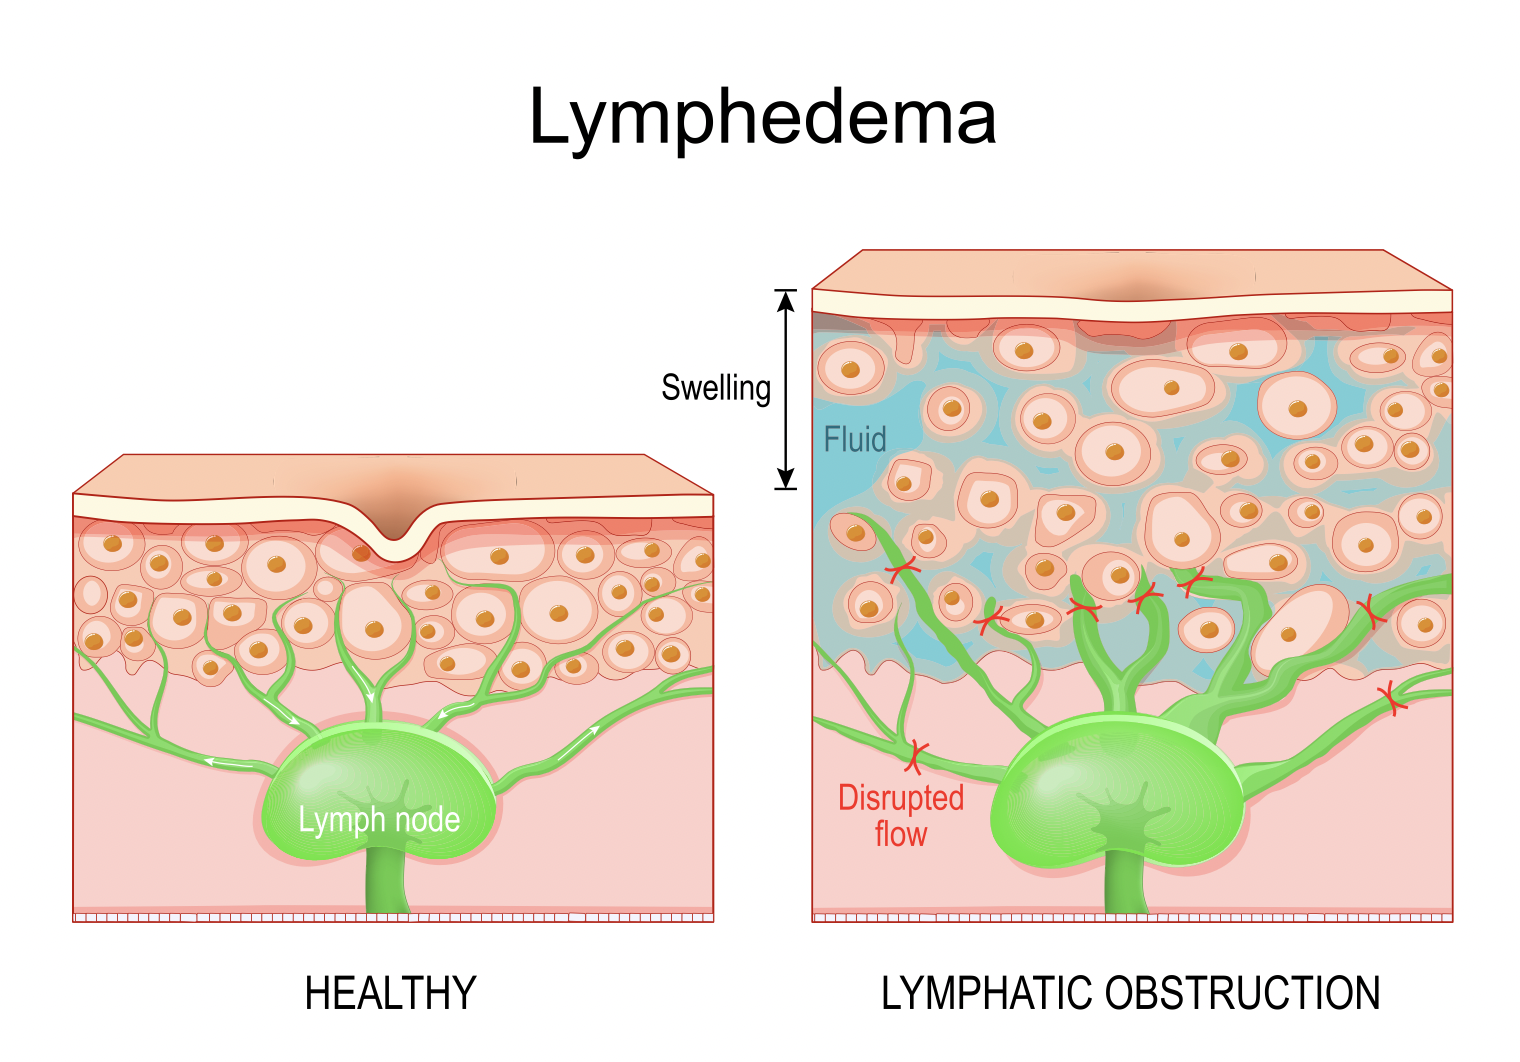

文章评论:手部治疗中的最佳水肿管理技术

Miller, LK、Jerosch-Herold, C. 和 Shepstone, L. (2017)。亚急性手部水肿水肿管理技术的有效性:系统评价。手部治疗杂志,30(4), 432-446。 ...